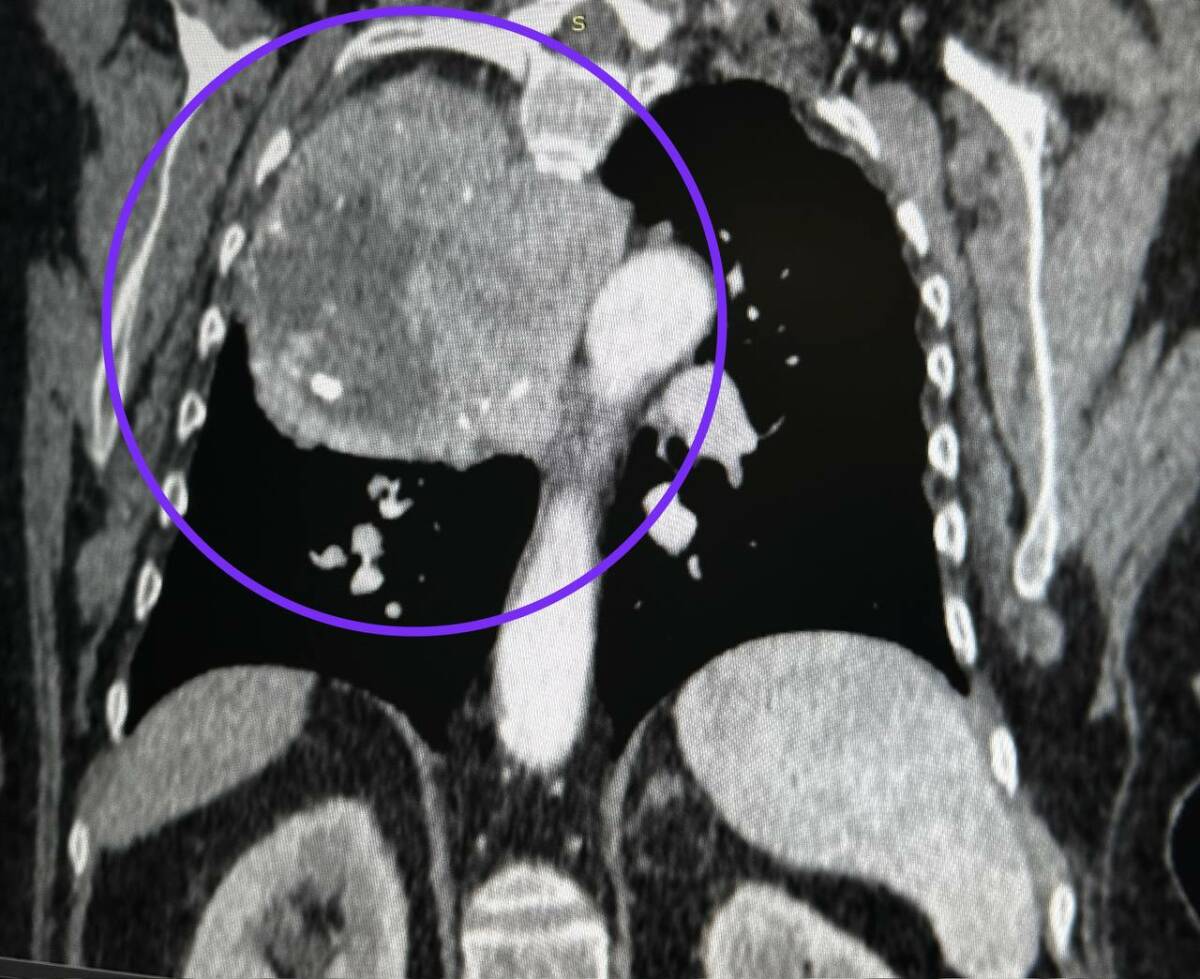

Торакальные хирурги РКБ Татарстана провели операцию по удалению крупного образования из грудной клетки 75-летней пациентки. Об этом сообщает пресс-служба медучреждения.

Еще в 2017 году подобные симптомы позволили выявить аномально увеличенную щитовидную железу, расположенную нетипичным образом. Тогда врачам пришлось провести удаление опухоли практически со всей железой. Но в этот раз опухоль выросла из нижнего полюса щитовидной железы и заняла треть грудной клетки.

Фото: Пресс-служба РКБ Татарстана

Как отметили врачи, в их практике такое образование встречается впервые. Хирурги успешно выполнили операцию, удалив опухоль через разрез между ребер за три часа.